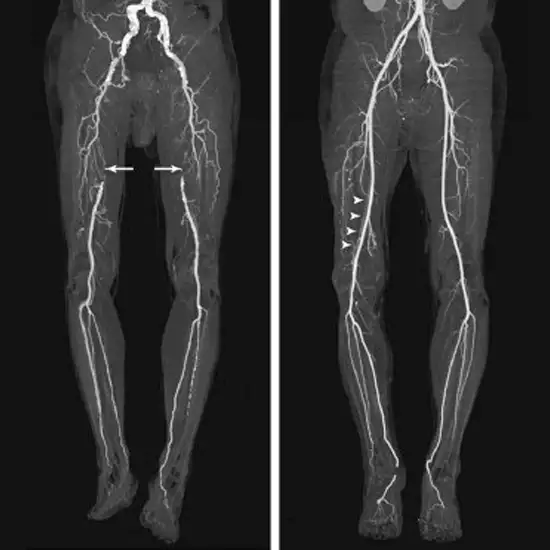

A CT Angio Right Lower Limb is an imaging test in which a contrast medium is used to diagnose the vascular injury of the Right lower limb.

In this procedure, you need to lie supine on a table and your legs are placed towards the gantry. The cannula is inserted in your arm and then dye is injected through a cannula ( 90-100ML) while performing the scan.